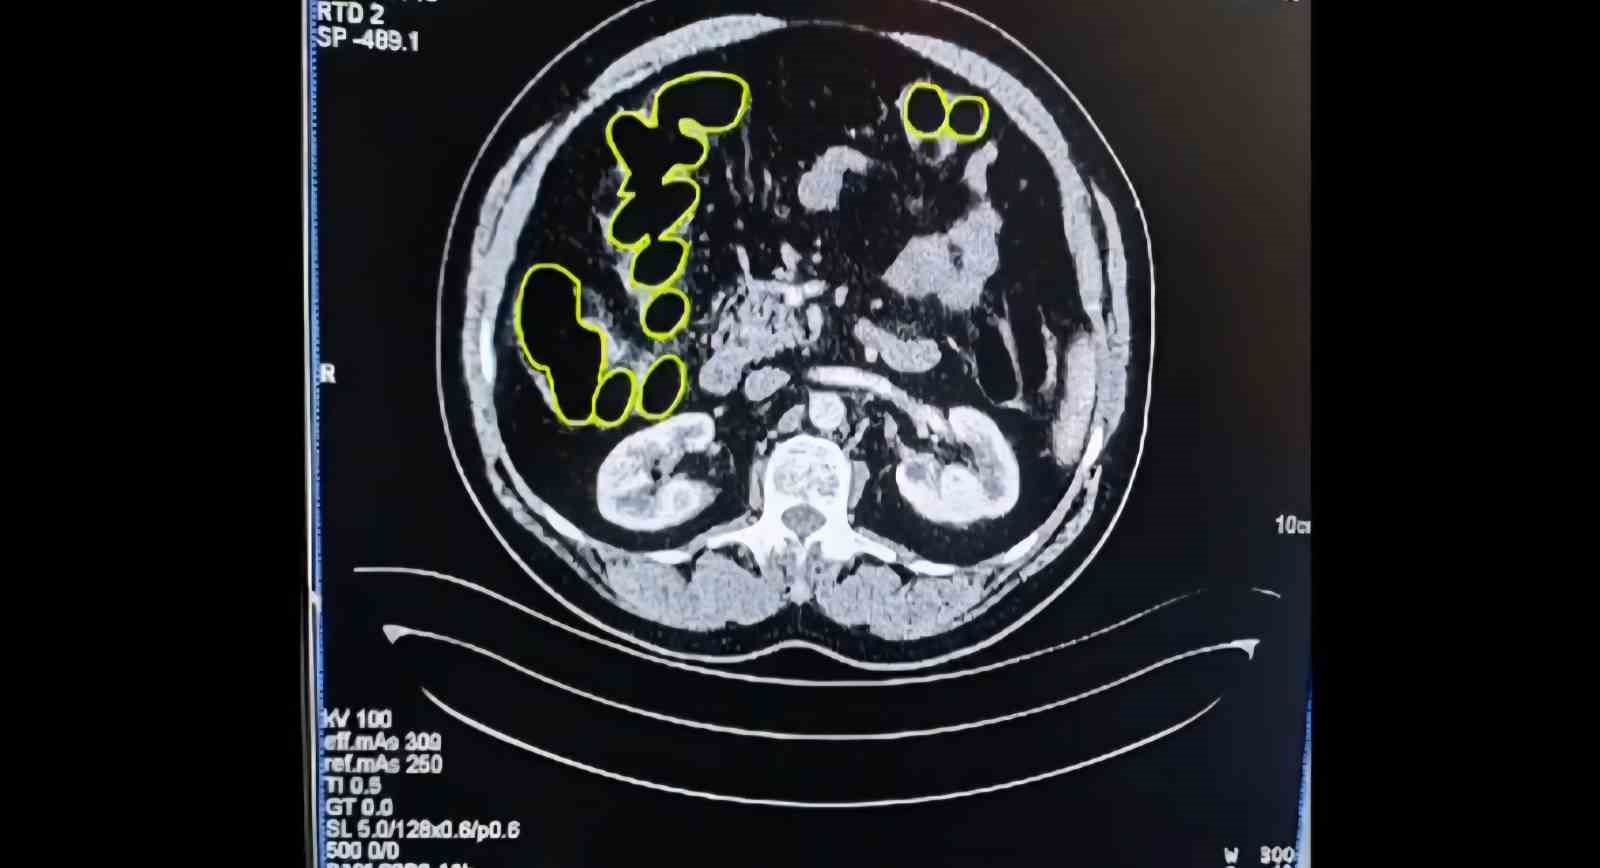

Şüphelilerin Kayseri Şehir Hastanesinde iç beden muayenesine alınırken, mide ve bağırsaklarında da çok miktarda kapsül şeklinde uyuşturucu olduğu değerlendirilen yabancı maddeler tespit edildi.